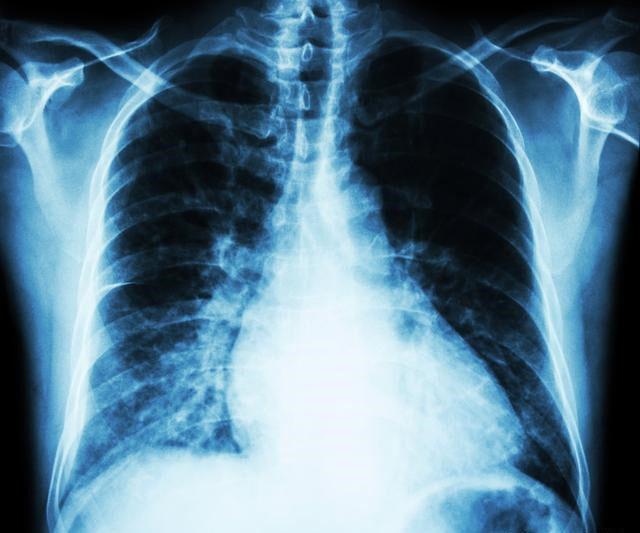

小细胞肺癌在所有肺癌病人中占15-20%,恶性程度高,容易通过血液和淋巴道转移,转移发生早而且广泛。由于小细胞肺癌与其他肺癌有完全不同的特性,因此分期方法有所不同,除了TNM分期,常用美国退伍军人分期标准,分为局限期和广泛期。局限期小细胞肺癌的特点是肿瘤局限于一侧胸腔内,包括有锁骨上或前斜角肌淋巴结转移和同侧胸腔积液。当病变超出局限期范围,均称为广泛期。